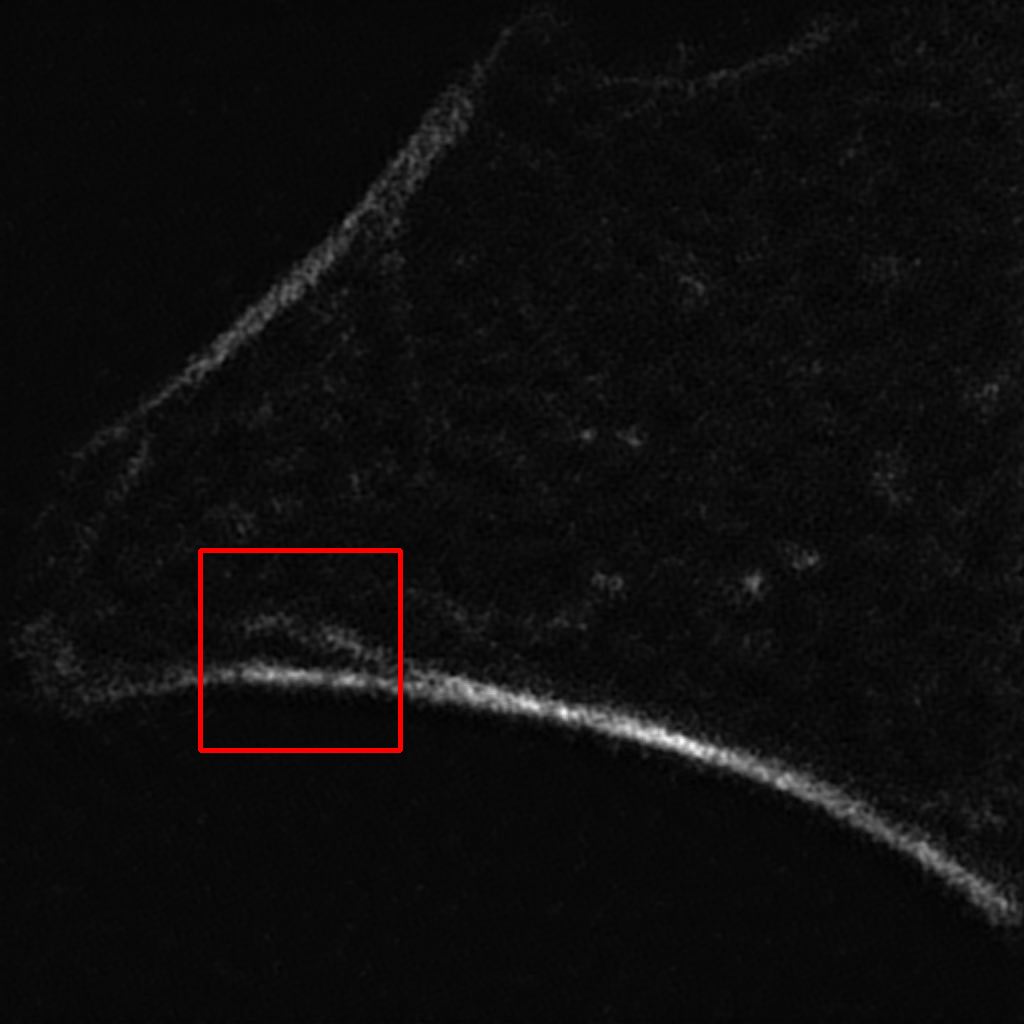

(a) Bicubic

(20.35 / 0.41)

Refer to caption

(b) Output

(24.96 / 0.741)

(c) SIM

a

Figure 8: Results of our algorithm on an unseen image in the W2S dataset [13]. (a) Low resolution widefield image upscaled using bicubic interpolation. (b) Output of our model in our final solution. (c) Corresponding image obtained using a SIM process. PSNR and SSIM values are, respectively, shown in parenthesis. Images on the second row are zoomed up regions highlighted by red boxes on the full images.

It can be observed in Figure 8 that, even though not perfect, the denoising is very effective and that the textures and details of the image are well approximated when compared to the ground truth SIM image.